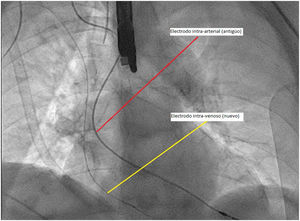

La paciente es llevada a quirófano donde, previa a la retirada del electrodo en cuestión, es insertado vía transvenosa un nuevo electrodo de estimulación, y conectado a uno nuevo generado al ser la paciente dependiente de marcapasos (fig. 4).